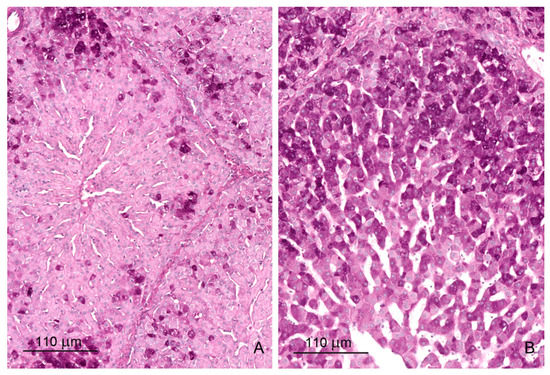

2.1. Light Microscopy Study

2.1.1. Architecture of the Liver

2.1.2. Microscopic Liver Scoring

2.1.3. Hepatic Sinusoids

2.1.4. Glycogen Storage

2.1.5. Iron Deposits